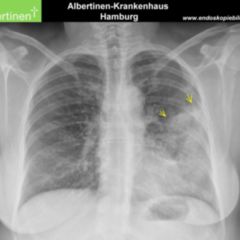

Aufgrund der diffusen Ausbreitung des invasiv lobulären Karzinoms und der äußerst seltenen Bildung von Mikrokalk kann das Ausmaß der Tumorausbreitung innerhalb der Brustdrüse fast nur mit der MRT und nicht mit der Mammographie festgestellt werden.